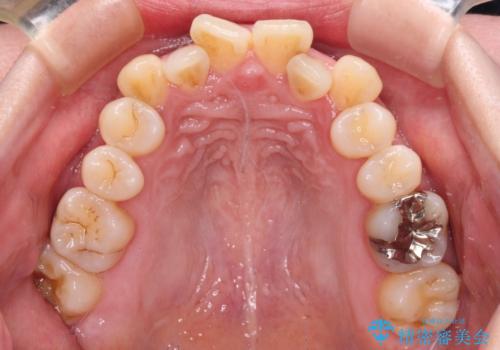

- 上下前歯のデコボコと、上顎の八重歯を気にして来院された患者様です。

下顎に対して上顎が前方にあり、第一大臼歯による咬合状態は上顎前突であったため、上顎のみ左右の第一小臼歯を抜歯し、ワイヤー装置にて矯正治療を行うこととしました。

舌の突出癖が強く、治療途中で上下前歯が乖離した開咬となってしまいました。

舌のトレーニングで開咬は改善できますが、なかなかトレーニングが進まず、治療期間は想定よりも長期化してしまいました。